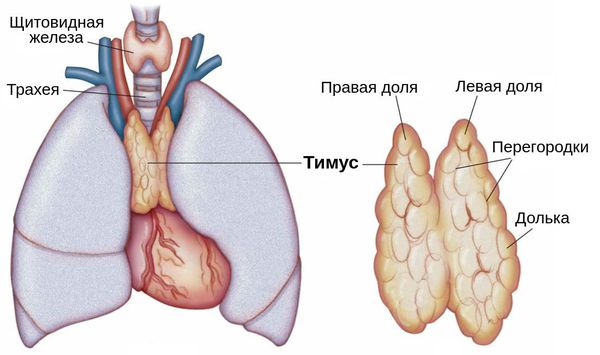

Тимомегалия: что это такое и как проявляется